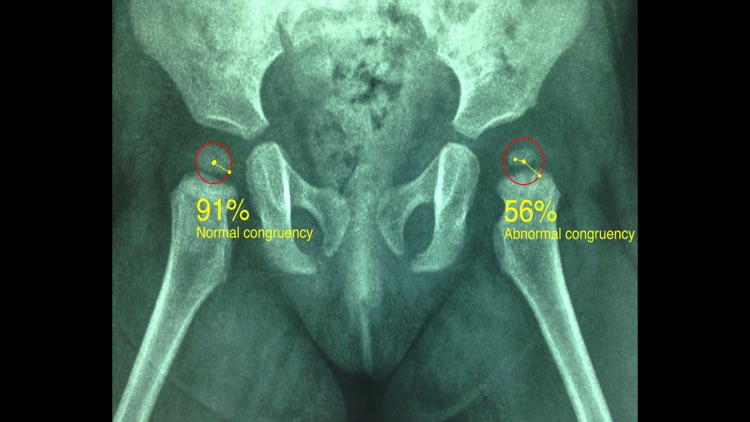

Congruence is present when the center of the femoral head (ball) and that of the acetabulum (socket) coincide. Lack of hip congruence between the femoral head and the acetabulum leads to increased local contact stresses, degeneration and consequently to premature arthritis. Although corrective hip osteotomies for the realignment of the dysplastic acetabulum is the main goal of treatment strategies, if the joint space congruency remain fair this end up in failure. Joint congruency can be rated subjectively according to the surgeons experience but according to international literature, evaluation and monitoring hip joint congruency is crucial to judge and predict the outcome of treatment. The App measures objectively the congruence and gives values as percentage (Congruence Index) which can be used for evaluation or comparisons of treatments modalities like acetabular osteotomies in developmental dysplasia or Legg-Calve-Perthes disease of the hip.

-Offers a very convenient and most accurate possibly way to determine joint space congruency with two methods. With transparent circular template-Moses template- you try to find the best-fitted circle superimposed over the femoral head, you mark the femoral head center and with the same manner you locate the acetabular center of the weight bearing zone. When the center of the best-fitted circle of the acetabulum coincide with the center of the femoral head, the concruency of the joint is considered normal (CnI =100%).The app calculates automatically the congruency index. The results are printed as a percentage of congruency of the hip joint and the hip is categorized as normal or abnormal.